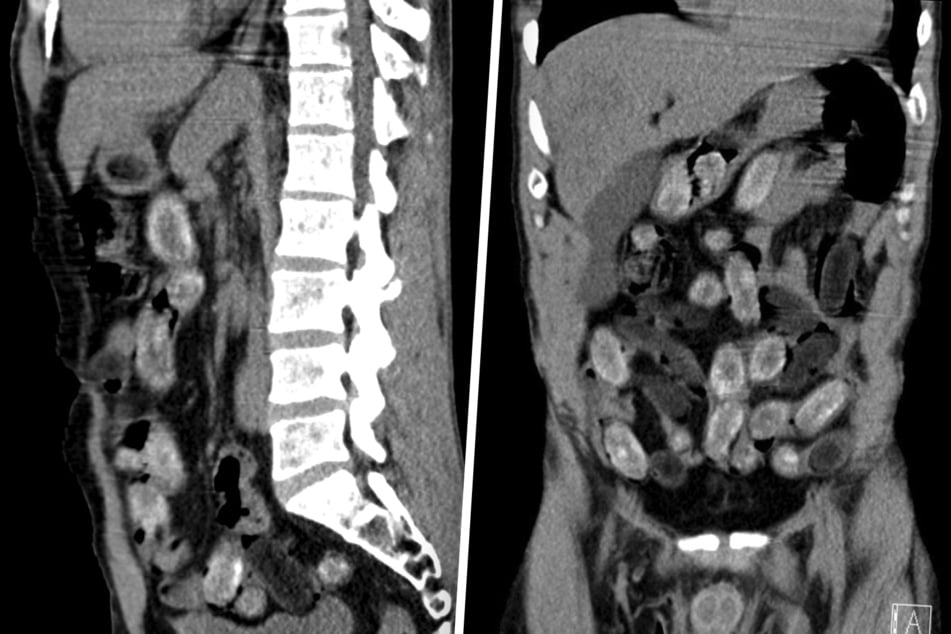

Eine Röntgenaufnahme in einem nahe gelegenen Krankenhaus bestätigte schließlich den Verdacht der Ermittler: Der komplette Magen-Darm-Trakt des Mannes war voller Drogenpäckchen.

Unter medizinischer Aufsicht schied der Mann die Päckchen nach und nach aus. Insgesamt 75 Bodypacks, gefüllt mit rund 450 Gramm Kokain und etwa 300 Gramm Heroin, hatte der 31-Jährige geschluckt.